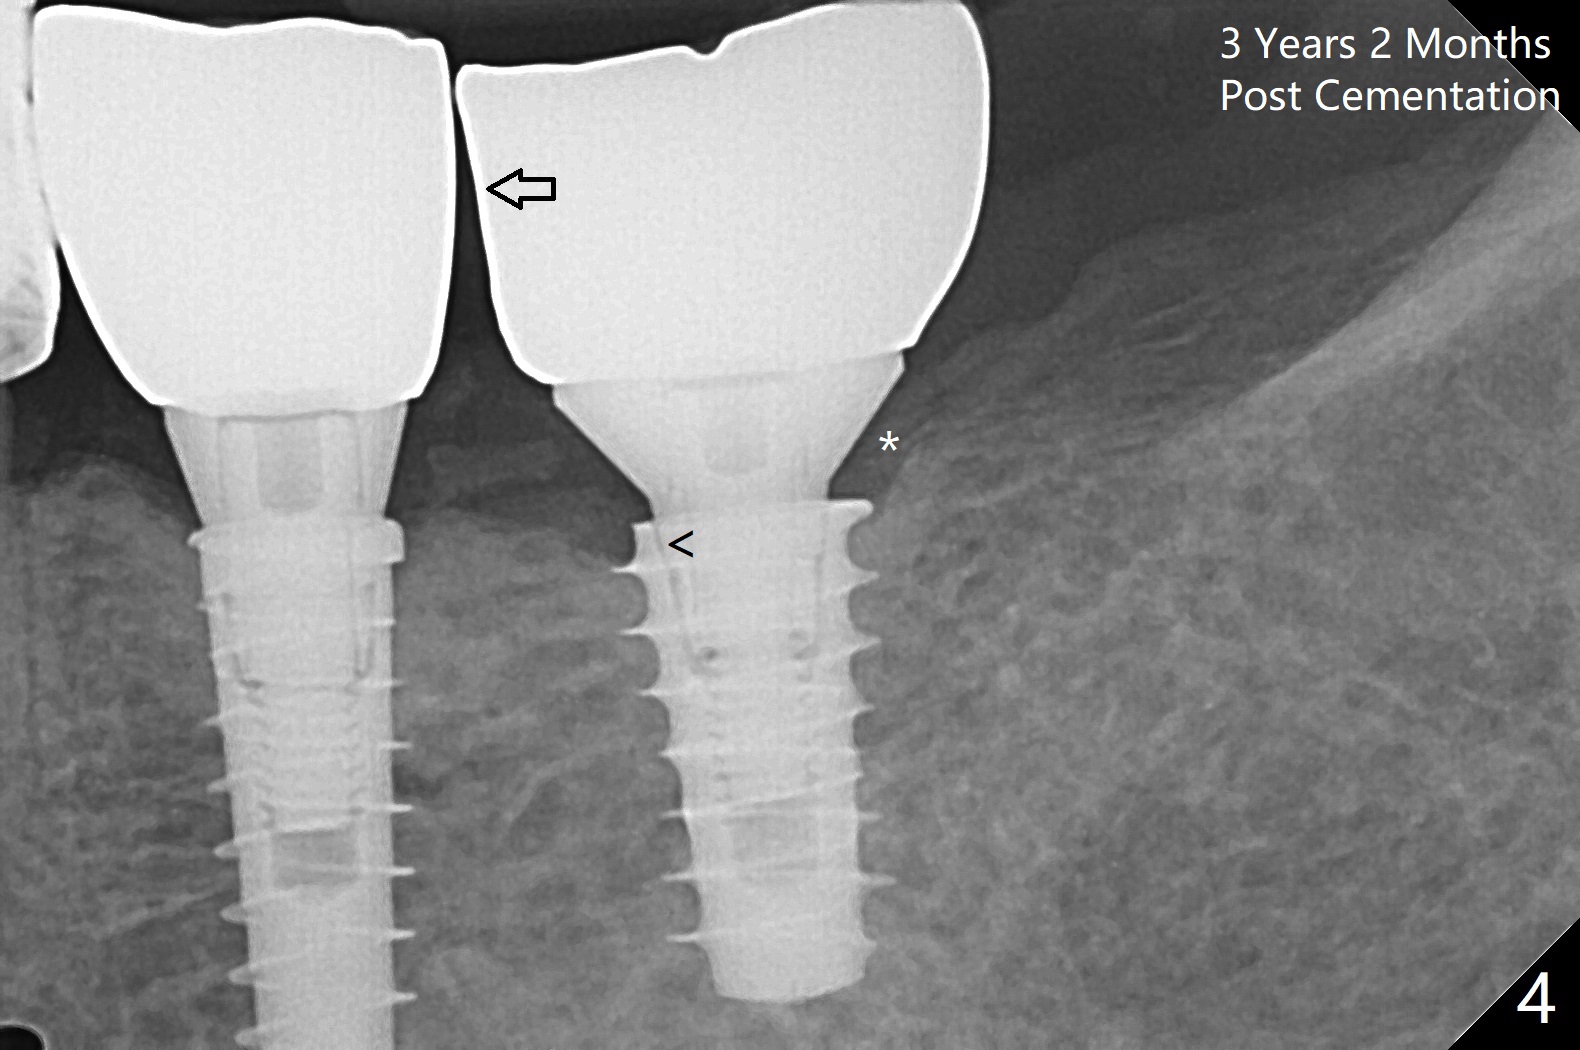

Because of the narrow ridge top at the sites of #19 and 18, it is reduced (Fig.1 arrowheads) prior to initial osteotomy with 1.6 mm pilot drill.  After Magic Drills (3.3 and 4.3 mm at #19 and 18, respectively), 4x11 and 5x9 mm IBS implants are placed with insertion torque >35 Ncm with immediate placement of pair abutments (4.5x5.7(2) and 6.5x4(2) mm, Fig.2).  In fact these sites are converted to a premolar and a 1st molar (because narrow ridge at #19).  Following GBR and suturing, periodontal dressing is applied around the abutments for increased retention.  The regional ridge reduction makes Marking Bur unnecessary (because of flat ridge top and the soft bone in this case) and more importantly there is no thread exposure upon implant placement.  The trimmed site (concavity) is favorable for bone graft and membrane placement.  One month postop, loose perio dressing is removed and replaced by a splinted nonfunctional provisional.  The implant sites look normal nearly 3 months postop; there is no bone loss (Fig.3).  Impression is taken.  The crown/abutment at #18 is loose 3 years 2 months post cementation; when the crown/abutment is retightened, the abutment remains incompletely seated (Fig.4 <) in spite of reduction of the proximal contact (arrow).  It may be due to the block of the distal crest (*).  After use of 5.5 mm profile drill, the 6.5x4(2) mm abutment remains unseated (Fig.5).  The smaller one (5x4(2) mm, Fig.6) is seated.  When the redo crown is cemented, the surrounding gingiva is healthy with a short papilla between the implant crowns (Fig.7).